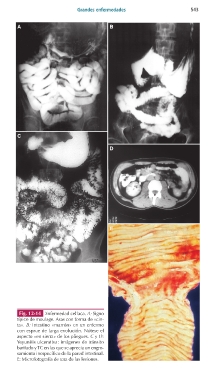

Fig. 12-14 Enfermedad celíaca. A: Signo

típico de moulage. Asas con forma de «cin-

ta». B: Intestino «marrón» en un enfermo

con esprue de larga evolución. Nótese el

aspecto «en sierra» de los pliegues. C y D:

Yeyunitis ulcerativa: imágenes de tránsito

baritado y TC en las que se aprecia un engro-

samiento inespecífico de la pared intestinal.

E: Microfotografía de una de las lesiones.